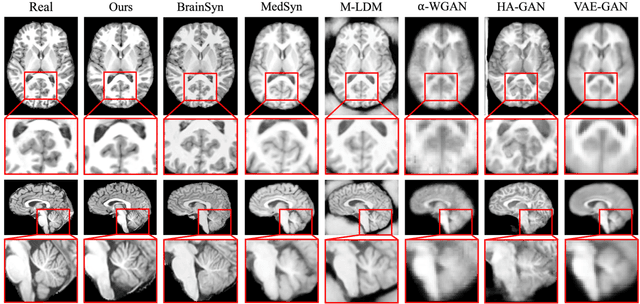

3D brain MRI studies often examine subtle morphometric differences between cohorts that are hard to detect visually. Given the high cost of MRI acquisition, these studies could greatly benefit from image syntheses, particularly counterfactual image generation, as seen in other domains, such as computer vision. However, counterfactual models struggle to produce anatomically plausible MRIs due to the lack of explicit inductive biases to preserve fine-grained anatomical details. This shortcoming arises from the training of the models aiming to optimize for the overall appearance of the images (e.g., via cross-entropy) rather than preserving subtle, yet medically relevant, local variations across subjects. To preserve subtle variations, we propose to explicitly integrate anatomical constraints on a voxel-level as prior into a generative diffusion framework. Called Probabilistic Causal Graph Model (PCGM), the approach captures anatomical constraints via a probabilistic graph module and translates those constraints into spatial binary masks of regions where subtle variations occur. The masks (encoded by a 3D extension of ControlNet) constrain a novel counterfactual denoising UNet, whose encodings are then transferred into high-quality brain MRIs via our 3D diffusion decoder. Extensive experiments on multiple datasets demonstrate that PCGM generates structural brain MRIs of higher quality than several baseline approaches. Furthermore, we show for the first time that brain measurements extracted from counterfactuals (generated by PCGM) replicate the subtle effects of a disease on cortical brain regions previously reported in the neuroscience literature. This achievement is an important milestone in the use of synthetic MRIs in studies investigating subtle morphological differences.